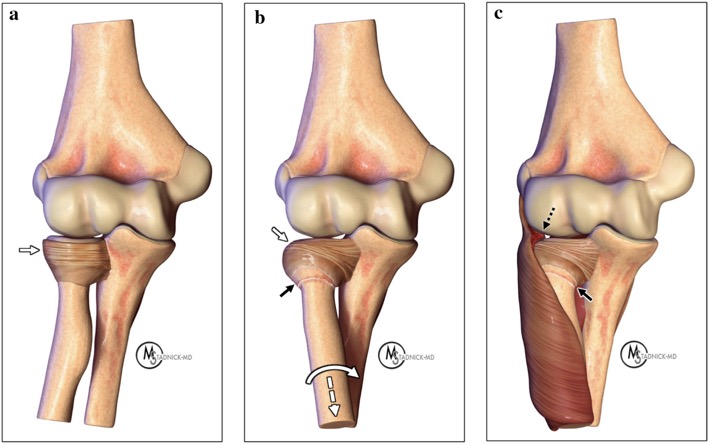

A Alignement normal et position anatomique du ligament annulaire.

B Lorsque la traction (flèche blanche pointée) et la pronation (flèche blanche incurvée) sont appliquées sur l'avant-bras, les fibres distales du ligament annulaire sont perturbées (flèches noires) et la partie antérieure de la tête radiale s'échappe sous la partie antérieure du ligament annulaire (flèche blanche).

C Piégeage du ligament annulaire et de l'attachement du supinateur (flèche pointillée noire) entre la tête radiale et le capitellum.